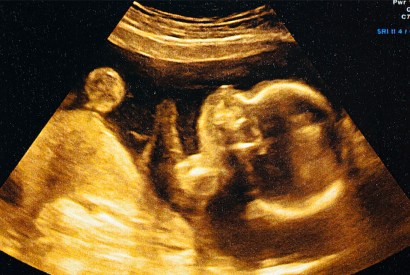

I’ll be forever grateful to my son’s surrogate